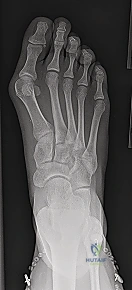

2. التصوير الشعاعي المتقدم (X-Rays)

تُعد الأشعة السينية أثناء الوقوف (Weight-bearing X-rays) حجر الأساس في التشخيص وتحديد خطة الجراحة. يقوم الأستاذ الدكتور محمد هطيف بقياس زوايا دقيقة جداً لتحديد شدة التشوه، وهي:

* زاوية إبهام القدم الأروح (HVA): الزاوية بين المشط الأول والسلامية الدانية. (الطبيعي أقل من 15 درجة).

* الزاوية بين الأمشاط (IMA): الزاوية بين المشط الأول والمشط الثاني. (الطبيعي أقل من 9 درجات).

* زاوية المفصل القاصي (DMAA): تقيم مدى انحراف سطح المفصل نفسه.

* تقييم صفائح النمو: التأكد من حالة صفائح النمو (مفتوحة أم مغلقة) وهو ما يحدد نوع الجراحة الممكنة.